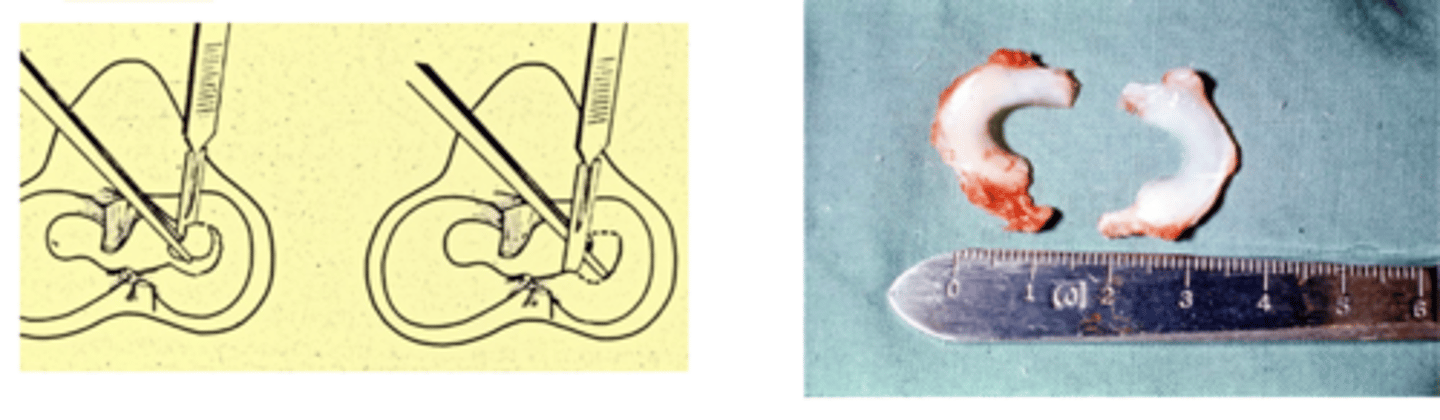

1. transection of meniscotibial ligament...A in the image

2. transection of midbody meniscus....B in the image

what are the location of release of the medial meniscus...process of protecting medial meniscus following sx. stabilization of the stifle in a procedure such as a TPLO

total meniscectomy

what procedure is shown here

only when peripheral rim of meniscus is so damaged that the primary suturing of meniscocapsular tissue is not possible

when is total meniscectomy considered